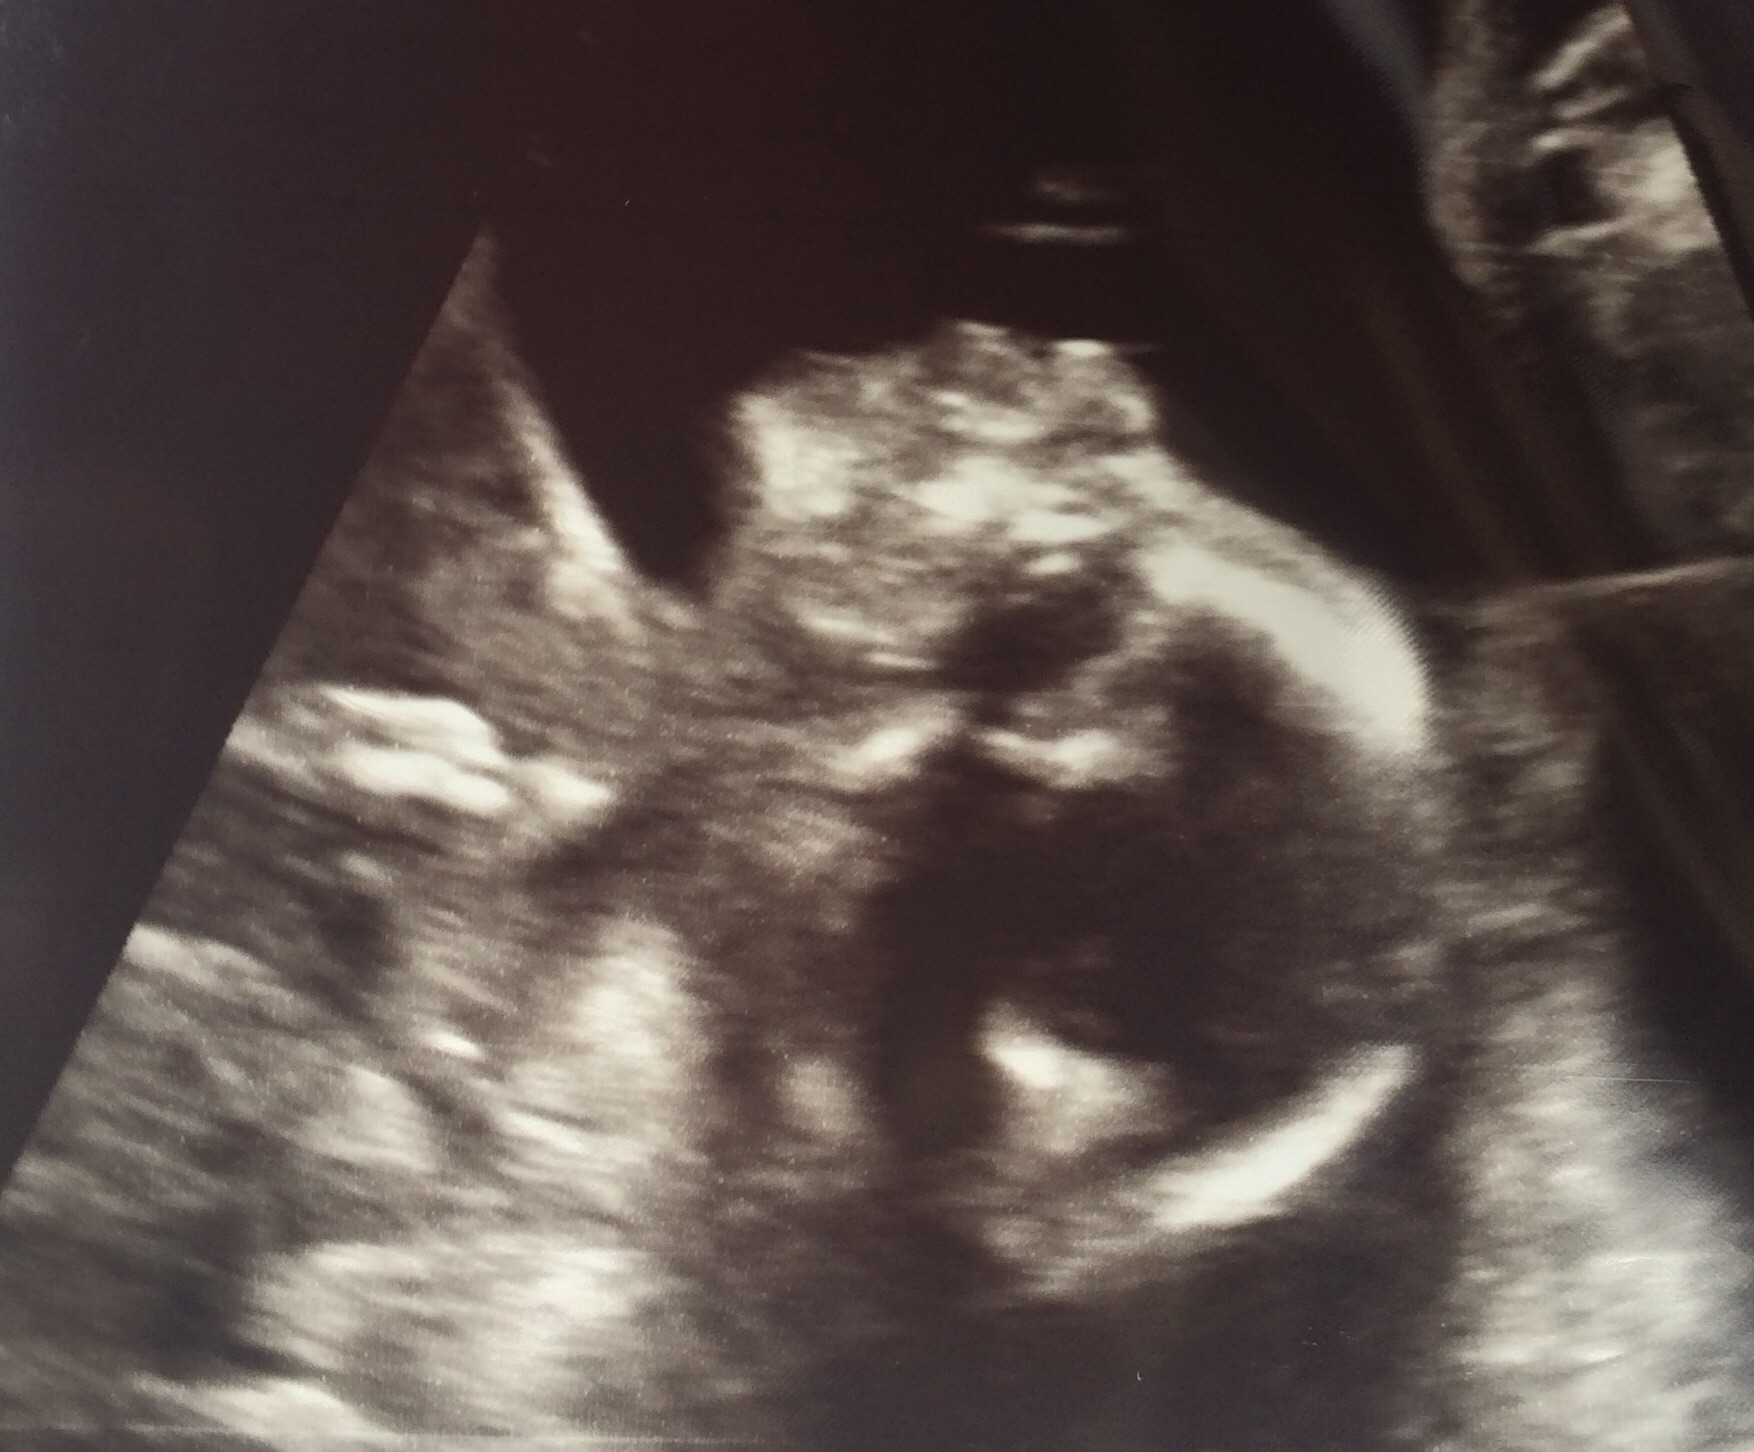

Here is my little one. No pics of me yet as I can't manage to take a good selfie. I will have my husband take one this weekend and post next week. 20 + 3 today. We had our ultrasound on Monday and stayed team green and still don't know what we are having. Everyone's pictures look great! Thanks everyone for sharing!